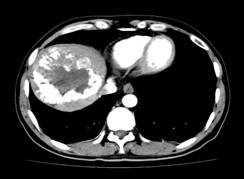

张××,男,56岁,外院CT增强示肝右叶“巨块型肝癌”,首次介入治疗后复查CT(2012年4月25日)所见瘤体大部栓塞,周围组织损伤小(图1a~b)。3年9个月后复查(2016年1月21日)见原瘤体明显缩小,上方肝实质复发病灶(图2a~b)。

图1a 图1b

图2a 图2b